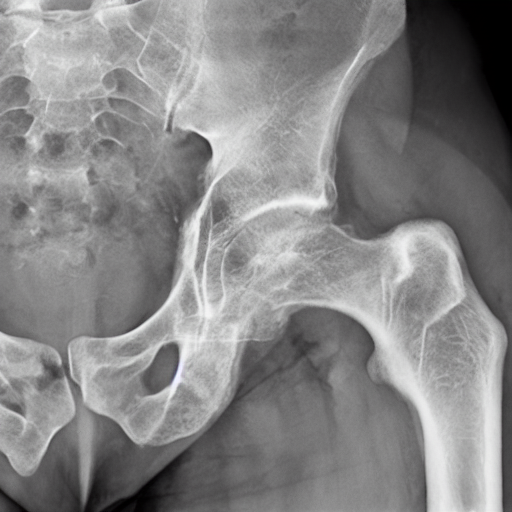

- Showing the subtrochanteric fracture in the porotic bone.

prompt = "Showing the subtrochanteric fracture in the porotic bone."

image = pipe(prompt).images[0]

image.save("porotic_bone_fracture.png")